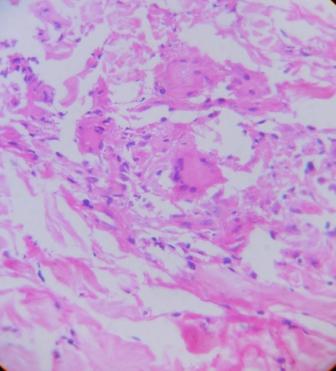

Annular elastolytic giant cell granuloma (AEGCG) is a rare granulomatous dermatosis characterized by loss of elastic fibers and elastophagocytosis by multinucleated giant cells. It is characterized by annular plaques that are similar to those observed in granuloma annulare but that specifically appear in sun-exposed skin and occurs more commonly in females than males. There have been reported cases of AEGCG associated with diabetes mellitus, systemic sarcoidosis, cutaneous amyloidosis, molluscum contagiosum, squamous cell carcinoma of the lung and cutaneous T-cell lymphoma. We report a case of AEGCG in both sun-exposed as well as covered areas of a middle aged lady with hepatic nodules and Barrets esophagus.